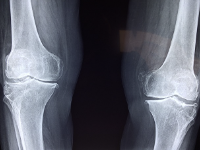

무릎 관절에 좋은 음식 무릎 관절 관리 방법 등 정보에 대해 알아보도록 하겠습니다. 무릎 관절은 우리 몸에서 가장 중요한 부위 중 하나입니다. 다리를 지탱하고, 움직임을 제공하는 기능을 수행합니다. 무릎 관절은 대개 체중과 운동에 의해 과부하가 걸리기 때문에, 연령과 상관없이 다양한 질환과 손상이 발생하기 쉽습니다. 무릎 관절 질환에는 퇴행성 관절염, 무릎 관절염, 슬관절 연골손상 등이 있습니다. 이러한 질환은 무릎 관절 통증, 붓기, 운동 제한 등의 증상을 유발합니다. 무릎 관절 건강을 유지하기 위해서는 적절한 운동, 올바른 식습관, 적절한 체중 유지, 적절한 자세 등이 필요합니다. 무릎 관절 질환의 예방과 관리를 위해서는 정기적인 건강 검진과 치료가 필요합니다.

무릎 관절염의 원인은 여러 가지가 있지만, 가장 일반적인 원인은 연령, 체중, 유전적인 요인, 부상, 직업적 요인, 불규칙한 운동 등이 있습니다.

- 연령: 노화로 인해 무릎 관절 손상이 발생할 가능성이 높습니다. 연령이 들면서 연골이 더 얇아지고 윤활유 분비가 감소하게 되어 무릎 관절의 충격 흡수 기능이 감소합니다.

- 체중: 과체중은 무릎 관절에 대한 부담을 높이며, 무릎 관절의 염증을 일으키고 무릎 관절염 발병 위험을 높입니다.

- 유전적 요인: 유전적 요인도 무릎 관절염의 원인 중 하나입니다. 가족력이 있는 경우 무릎 관절염 발병 위험이 높아집니다.

- 부상: 무릎 관절 부상은 무릎 관절염의 발병 위험을 높입니다. 특히, 골절, 연골손상, 인대 손상 등이 무릎 관절염을 일으키는 원인이 될 수 있습니다.

- 직업적 요인: 직업적 요인으로 인해 무릎 관절 부담이 커지면 무릎 관절염 발병 위험이 높아집니다. 예를 들어, 무릎을 자주 굽히거나 일어설 필요가 있는 직업, 장시간 서 있는 직업 등이 그러합니다.

- 불규칙한 운동: 무릎 관절 부하를 지나치게 높이는 불규칙한 운동은 무릎 관절의 염증을 유발합니다.

무릎 관절염은 위와 같은 여러 요인들이 복합적으로 작용하여 발생할 수 있습니다. 따라서 무릎 관절염 예방 및 치료를 위해서는 건강한 식습관과 운동 습관을 유지하며, 무릎 관절에 대한 적절한 관리가 필요합니다.